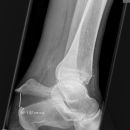

Osteomyelitis Calcaneus